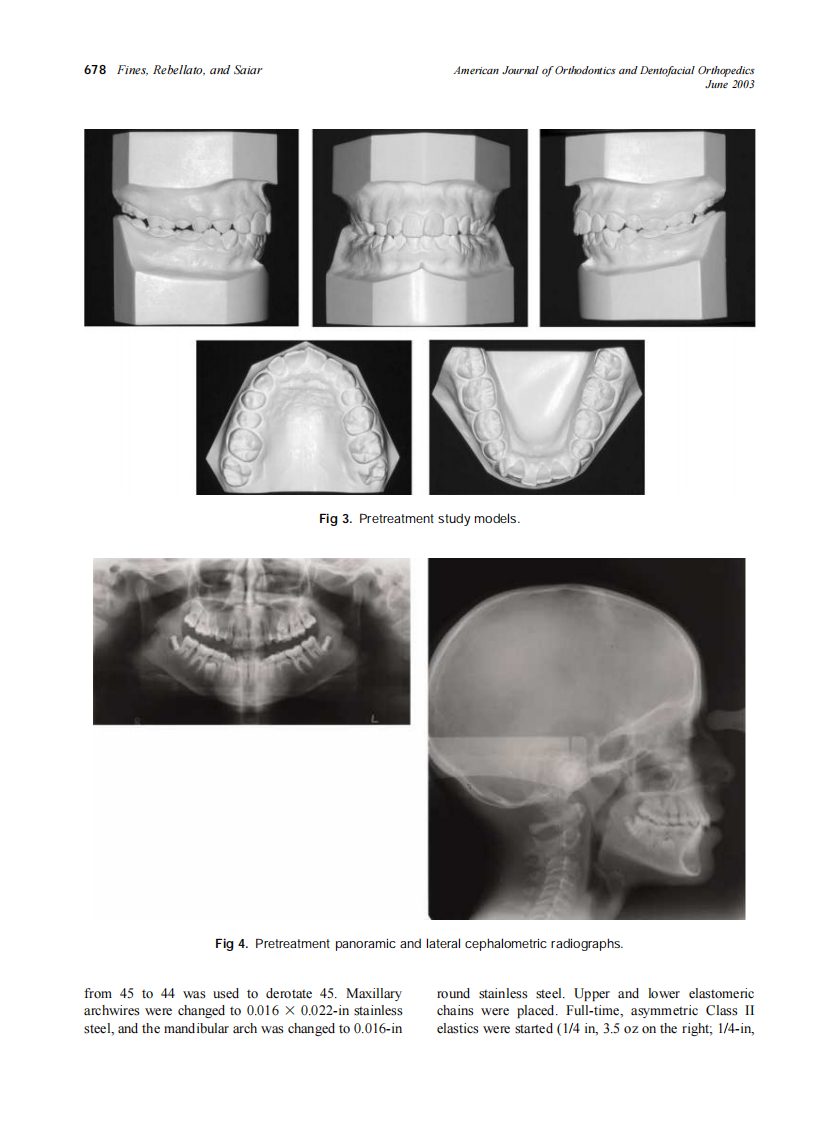

2003_123_6_676_682_Fines.pdf